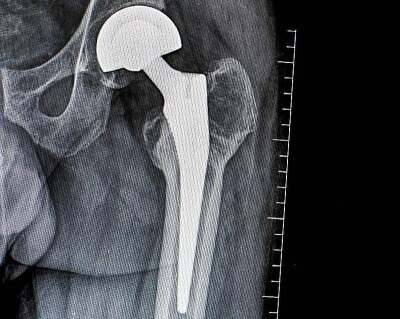

11 мая 2020

Остеоинтеграция имплантата в костную ткань при эндопротезировании тазобедренного сустава: стадии, механизмы, нарушения и факторы риска